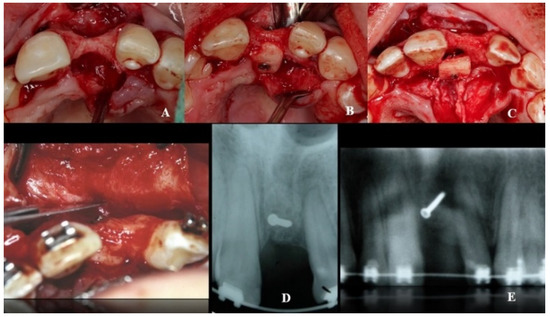

A double approach was used on the recipient jaw. On its vestibular aspect, compensating incisions were made distally on the lateral incisors (1.2 and 2.2), joined by an intrasulcular incision at the level of teeth 1.2 to 2.2, including a central incisor. A crestal incision was traced over the toothless residual ridge. A full-thickness trapezoidal flap was obtained upon curettage. On the palatal side, extensive curettage was performed to obtain a pocket covering the area from 1.2 to 2.2, thus exposing the bone defect and revealing the neurovascular bundle. The latter was next emptied with a bone scraper, and a 20 mm wide × 10 mm high cortico-cancellous block was obtained and placed palatally, covering the incisor foramen to increase the vestibulo–palatal width of the residual ridge. The blocks were held in position by titanium fixation micro-screws (BoneScrew kit® BioHorizons, Birmingham AL, USA) (Figure 4).

Figure 4.

Recipient area (A). Location of the bone block at the level of the foramen incisive (B) and on its incisal aspect (C). (D,E) Block fixation using fixing screws.

Combined application of autogenous bone and a xenograft (BioOss, Geistlich-Pharma AG, Schlieren, Switzerland) was then performed on the palatal, crestal, and vestibular aspects of the defect and canal areas, in order to increase the contour. A resorbable type I collagen membrane (Mem-Lok® RCM, BioHorizons, Birmingham, AL, USA) was then placed on the site, folded to cover the enlarged area, and attached with additional titanium tacks on the buccal side.